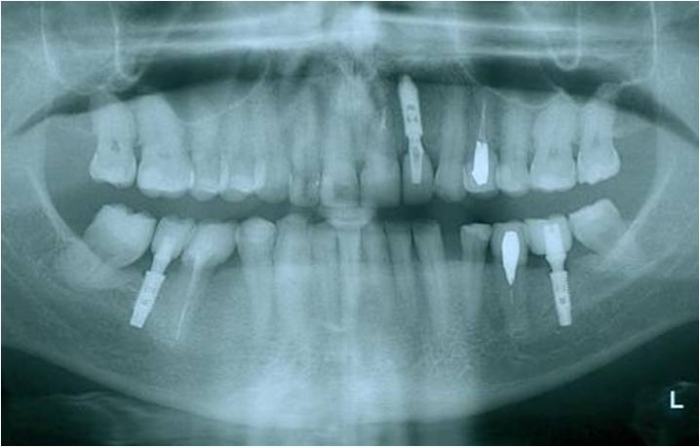

Raio X inicial